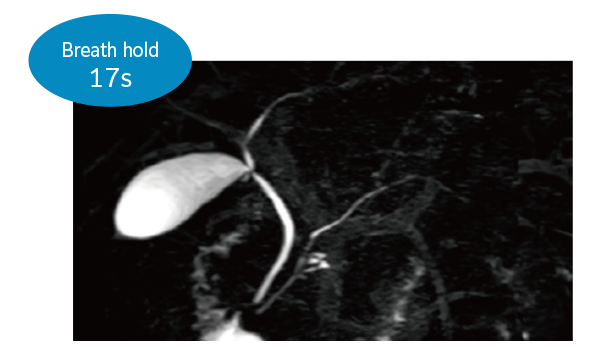

O IP-RAPID x DLR Plus oferece a flexibilidade de encurtar as séries com sincronização respiratória ou até mesmo substituí-las por prender a respiração, dependendo da situação do paciente. Isto oferece a você mais opções e uma gama mais vasta de exames à escolha.

3DMRCP (Apneia)

Gating do navegador 3DMRCP (Navi)

3DMRCP (Sincronização respiratória)